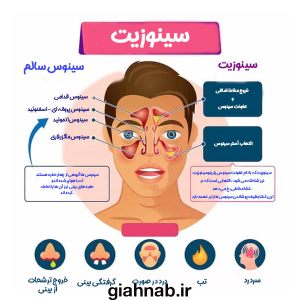

علائم سینوزیت

- گرفتگی و انسداد بینی

- ترشحات غلیظ و چرکی بینی

- سردرد و درد اطراف چشم و پیشانی

- تب و خستگی

- کاهش حس بویایی و چشایی

- سرفه بهویژه در شب

سینوزیت (Sinusitis) به التهاب یا عفونت سینوسهای پارانازال اطلاق میشود که معمولاً ناشی از عفونت